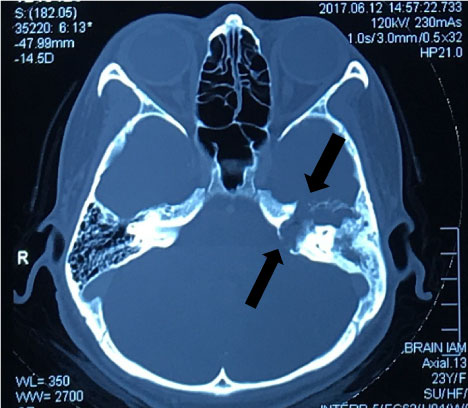

Cerebellar sign was negative. HRCT and MRI temporal bone revealed sclerosis of the mastoid bone with loss of mastoid air cells due to chronic mastoiditis. Soft tissue lesion and some fluid in the left middle ear and the attic of the tympanic canal. The left Eustachian tube also occluded with soft tissue lesion or secretion and does not enhance with intravenous contrast. There is bony erosion in the tegmen tympani and expansion of the petrous bone (Figure 1 and Figure 2). This finding suggest cholesteatoma in the left middle ear with erosion of the petrous bone and involvement of the left facial nerve canal. Patient then procced for transmastoid translabyrinthine approach.

Figure 1: CT mastoid. Shows bony expansion of the petrous bone with soft tissue lesion in the tympanic cavity and attic. View Figure 1

Figure 2: MRI brain and internal acoustic meatus (IAM). Shows bony expansion of the petrous bone with soft tissue lesion in the tympanic cavity and attic. View Figure 2